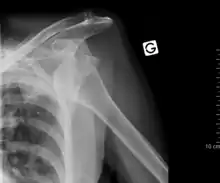

Anterior dislocation of the right shoulder. AP X ray -

Anterior dislocation of the right shoulder. Y view X ray. -

Fracture dislocation of the right shoulder